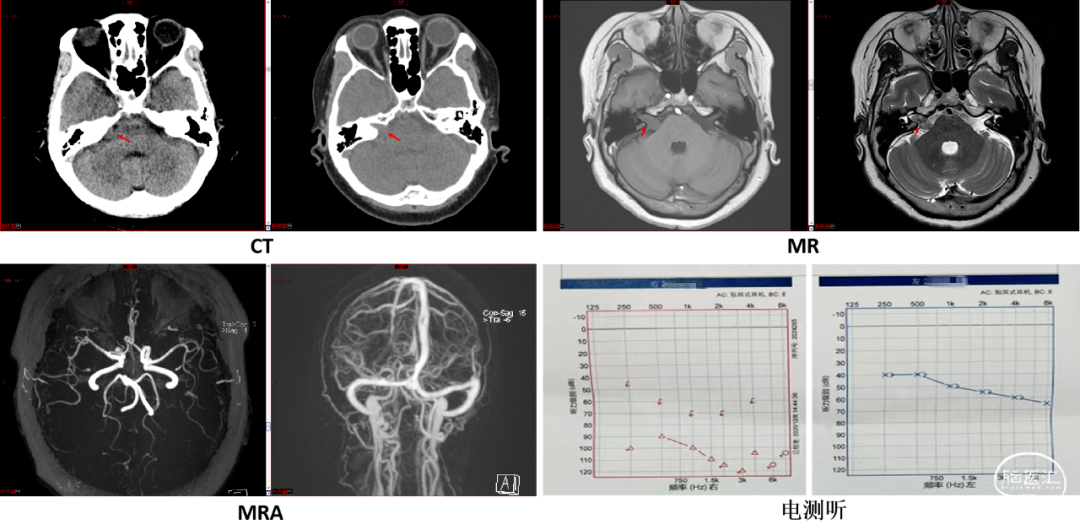

患者术后资料